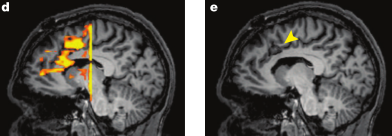

However, a recent study by Sheth et al (2012) in Nature examined six lesion patients undergoing cingulotomy, a surgical procedure which removes a localized portion of the dorsal anterior cingulate (dACC) in order to alleviate severe obsessive-compulsive symptoms, such as the desire to compulsively check the amount of hits your blog gets every hour. Before the cingulotomy, the patients performed a multisource interference task designed to elicit cognitive control mechanisms associated with dACC activation. The resulting cingulotomy overlapped with the peak dACC activation observed in response to high-conflict as contrasted with low-conflict trials (Figure 1).

Figure 1 reproduced from Sheth et al (2012). d) dACC activation in response to conflict. e) arrow pointing to lesion site